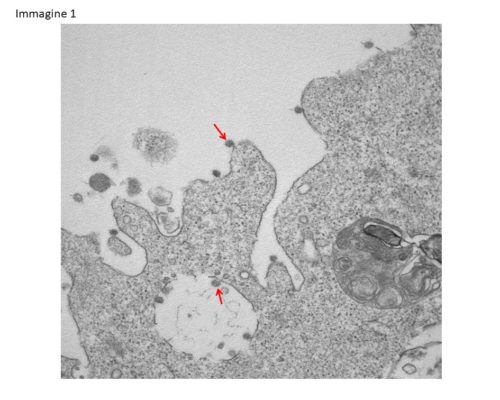

Nella foto si osservano chiaramente, ad un ingrandimento di 30000X, le particelle virali di Sars-CoV-2 (indicate dalle frecce), adese alle membrane sulla superficie e all?interno di cellule Vero E6 utilizzate per l?isolamento. (Foto: Statale di Milano)

Funzionano gli anticorpi generati nei topi dal vaccino italiano dell’azienda Takis: lo indicano i test eseguiti nel laboratorio di Virologia dell’istituto Spallanzani. Lo ha detto all’ANSA l’amministratore delegato Luigi Aurisicchio. E’ il livello più avanzato finora raggiunto nella sperimentazione di un candidato vaccino nato in Italia, ma i test sull’uomo sono previsti comunque dopo l’estate.